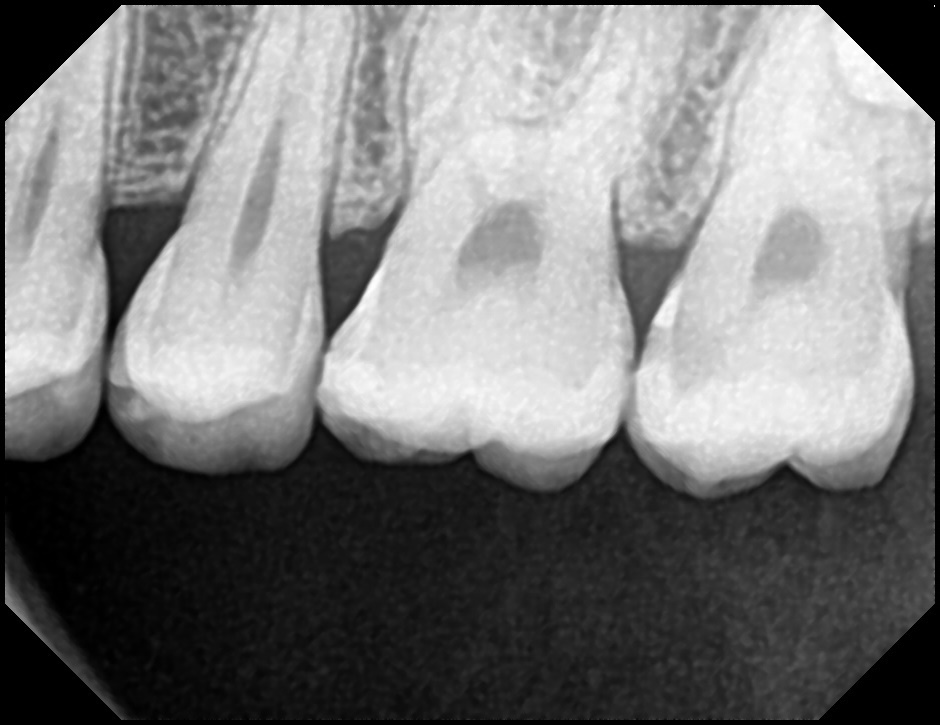

이와는 별개로 방사선 사진 상 치수강 위축이 관찰됩니다 이는 평소 딱딱한 음식을 자주 먹은 경우 잘 나타나는 증상입니다. 너무 딱딱하거나 질긴 음식은 자제하시기 바랍니다

평소 생활할 때 뜨거운 것이나 차가운 것에 민감한 반응을 보이거나 불편감이 1분이상 오래 지속되었다면 이는 충치가 신경에도 영향을 주었다는 것인데 그렇지 않다면 아주 깊은 충치는 아닌 것입니다.